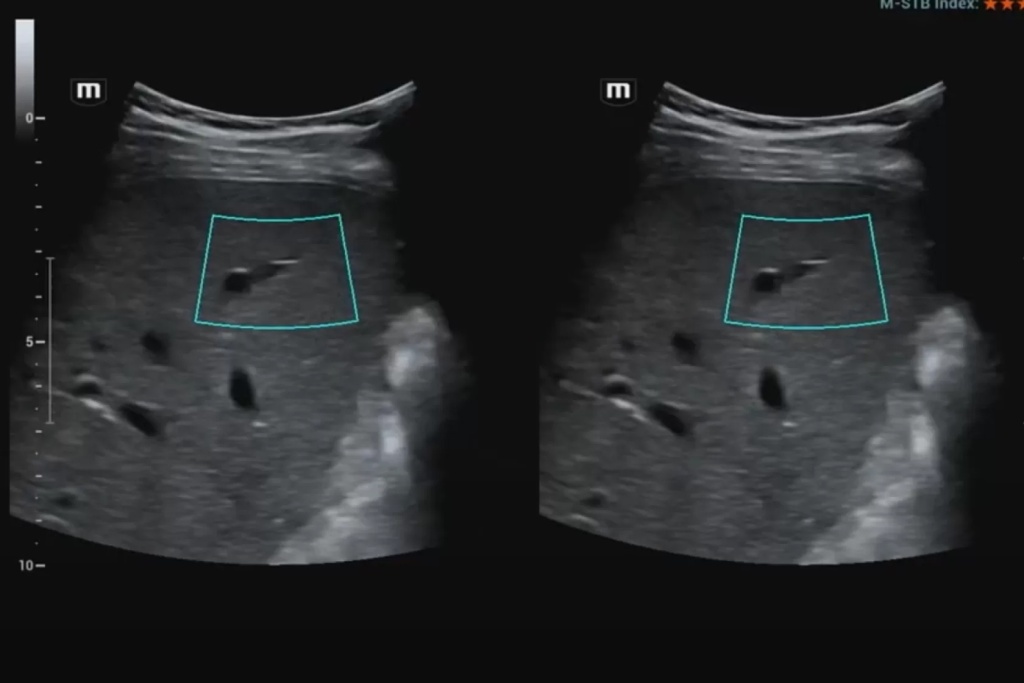

– Если не брать в расчет магнитно-резонансную эластографию и говорить только об ультразвуковой, то в зависимости от приложения силы, данный метод подразделяется на две большие группы: стрейновую эластографию (и наиболее распространенный ее вид – компрессионную) и эластографию сдвиговой волной.

В начале обсудим методику стрейновой эластографии. Она основана на сравнительной оценке деформации (или стрейнов) тканей в области интереса. Деформация может вызываться как приложенной мануальной компрессией, когда мы датчиком слегка надавливаем на подлежащие структуры, так и физиологическими явлениями – передаточной пульсацией сердца, сосудов, дыхательными движениями, а в некоторых случаях и усиленным акустическим импульсом.

В данном случае получение абсолютных значений модуля Юнга (характеризующего жесткость тканей) невозможно, так как его значения зависят от приложенной силы, величина которой не стандартизирована и неизвестна. Поэтому проводится сравнение величины деформации, или стрейна. При воздействии одинаковой силы менее деформируемые ткани являются более жесткими, а более деформируемые – менее жесткими. Ультразвуковой сканер, работающий в специальном режиме, позволяет оценить и сравнить величину деформации тканей в окне опроса и картировать их соответствующим цветом, а также провести полуколичественную оценку – определить отношение деформации в зоне интереса и референсной (условно здоровой) ткани – StrainRatio.

Эластография сдвиговой волной позволяет получить абсолютные значения жесткости исследуемой ткани. В основе данного метода лежит оценка скорости распространения поперечной (боковой) волны, которая может вызываться кратковременным механическим воздействием определенной силы и продолжительности на поверхность тела пациента (это так называемая транзиентная эластография) или сфокусированным усиленным акустическим импульсов в толще исследуемой ткани (именно данные методики в литературе обозначаются как эластография сдвиговой волной). Они в свою очередь подразделяются на методики точечной и двумерной эластографии.